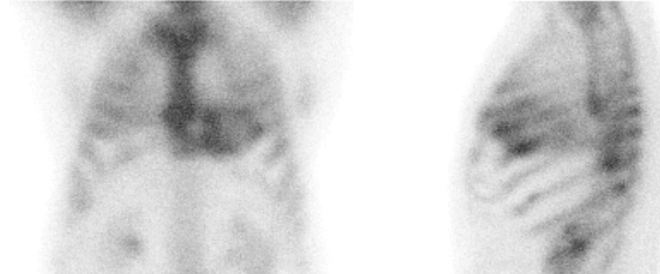

Za 3 hodiny po i. v. aplikaci 640 MBq 99mTc-DPD (butedronátu) (přípravek TECEOS) jsme provedli scintigrafická vyšetření na hybridní tomografické kameře Symbia T2 Intevo firmy Siemens a to statickou scintigrafii hrudníku v přední a levé boční projekci a následně gatovanou tomografickou scintigrafii (SPECT) myokardu.

/ Obr. č. 1: Statická scintigrafie hrudníku v přední a levé boční projekci. Vyšetření 3 hodiny po aplikaci radiofarmaka.

/

Prokazujeme zvýšenou depozici radiofarmaka v myokardu levé srdeční komory (nejvýrazněji v oblasti

septa) – dle semikvantitavní škály jde o stupeň 3.

Zvýšená depozice radiofarmaka v myokardu levé srdeční komory.

Scintigramy potvrzují transthyretinovou srdeční amyloidózu.